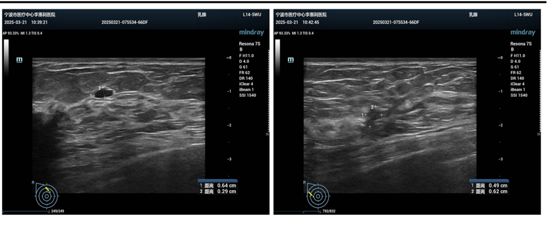

乳腺超声(2024 年 5 月14日):右乳结节(BI-RADS 4C 类),右乳片状低回声(BI-RADS 4A 类),右腋下实性占位(考虑转移性),左乳结节(BI-RADS 3 类)。

图1 2024年5月14日胸部CT